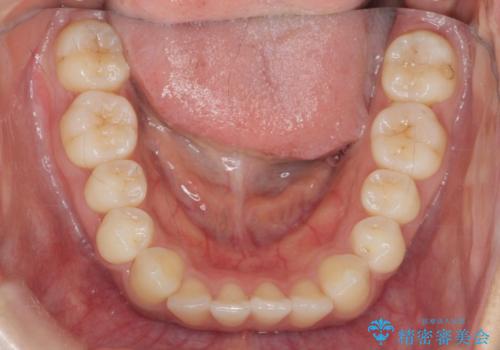

ワイヤー部分矯正を併用して治療期間を短縮 マウスピース矯正治療

- 前歯のガタつき、上下たがい違いになっている歯並び(クロスバイト)の改善を求めて来院されました。

インビザラインによる矯正治療を行いますが、クロスバイトの改善をワイヤー部分矯正で事前に行うことにより治療期間の短縮する治療計画を立案します。

上下すれ違った噛み合わせはマウスピースでは改善に時間がかかり、またねじれが残ってしまうことも多々見られます。

マウスピース矯正を行う前に、これらの症状の改善の得意なワイヤー部分矯正を行うことで治療期間を短縮し、確実にすれ違いを改善することができます。